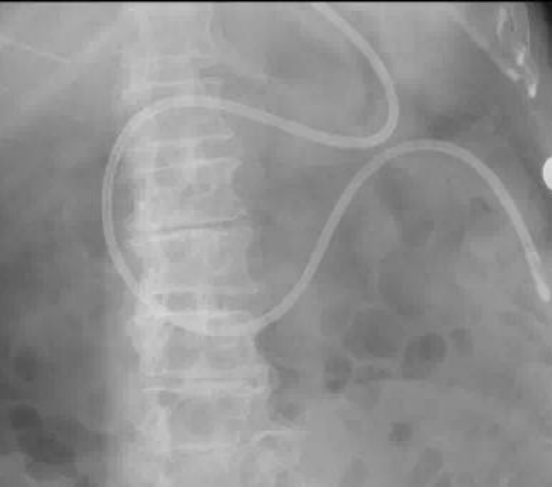

ICU护士长通过不断学习和临床实践,摸索出一套利用手法技巧和手感相结合的徒手床旁盲插鼻肠管置管技术,实现幽门后空肠喂养,解决了重症患者的营养通路的难题,该技术与以往的注水法和注气法不同,而是采用徒手压管推进法加听诊器导航进行鼻肠管置管术,最后经过听诊和X线验证,一个完美的“C”型,确认营养管已经到达空肠后为患者开通营养支持。